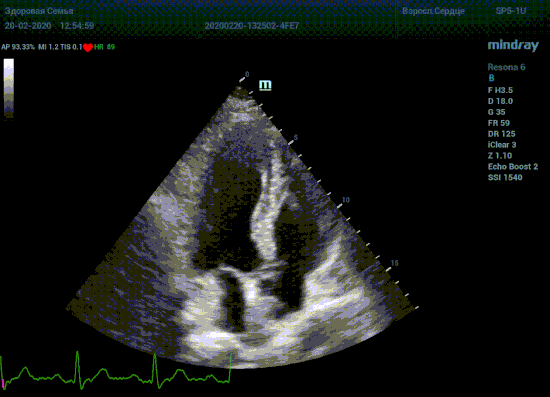

Специалисты в области эхокардиографии прекрасно знают о важности точного и скрупулёзного измерения. Рекомендации зарубежных кардиологических и эхо кардиографических обществ описывают эхокардиографию только под контролем ЭКГ. Многие клиники в России до сих работают без ЭКГ канала, выбирая кадры для измерения «на глазок». Результаты таких исследований менее точны и воспроизводимы, однако роль их очень и очень велика. Часть клиник используют ЭКГ отдельно от прибора, на бумаге. В таком виде для эхокардиографии она бесполезна, по сколку не создает временной карты для измерений.

Подбор подобающей терапии и оценка её динамики на базе расчета массы миокарды рутинная задача эхокардиографии. Для измерения массы нужен кадр конца диастолы. На глазок или точно, по ЭКГ каналу, выбрать диастолу? Гипертрофия миокарда или его ремоделирование? Ремоделирование или норма? Решает каждый измеренный миллиметр, даже каждая его десятая. Лишние доли секунды приведут к началу сокращения миокарда и его утолщению, в результате -гипердиагностика.